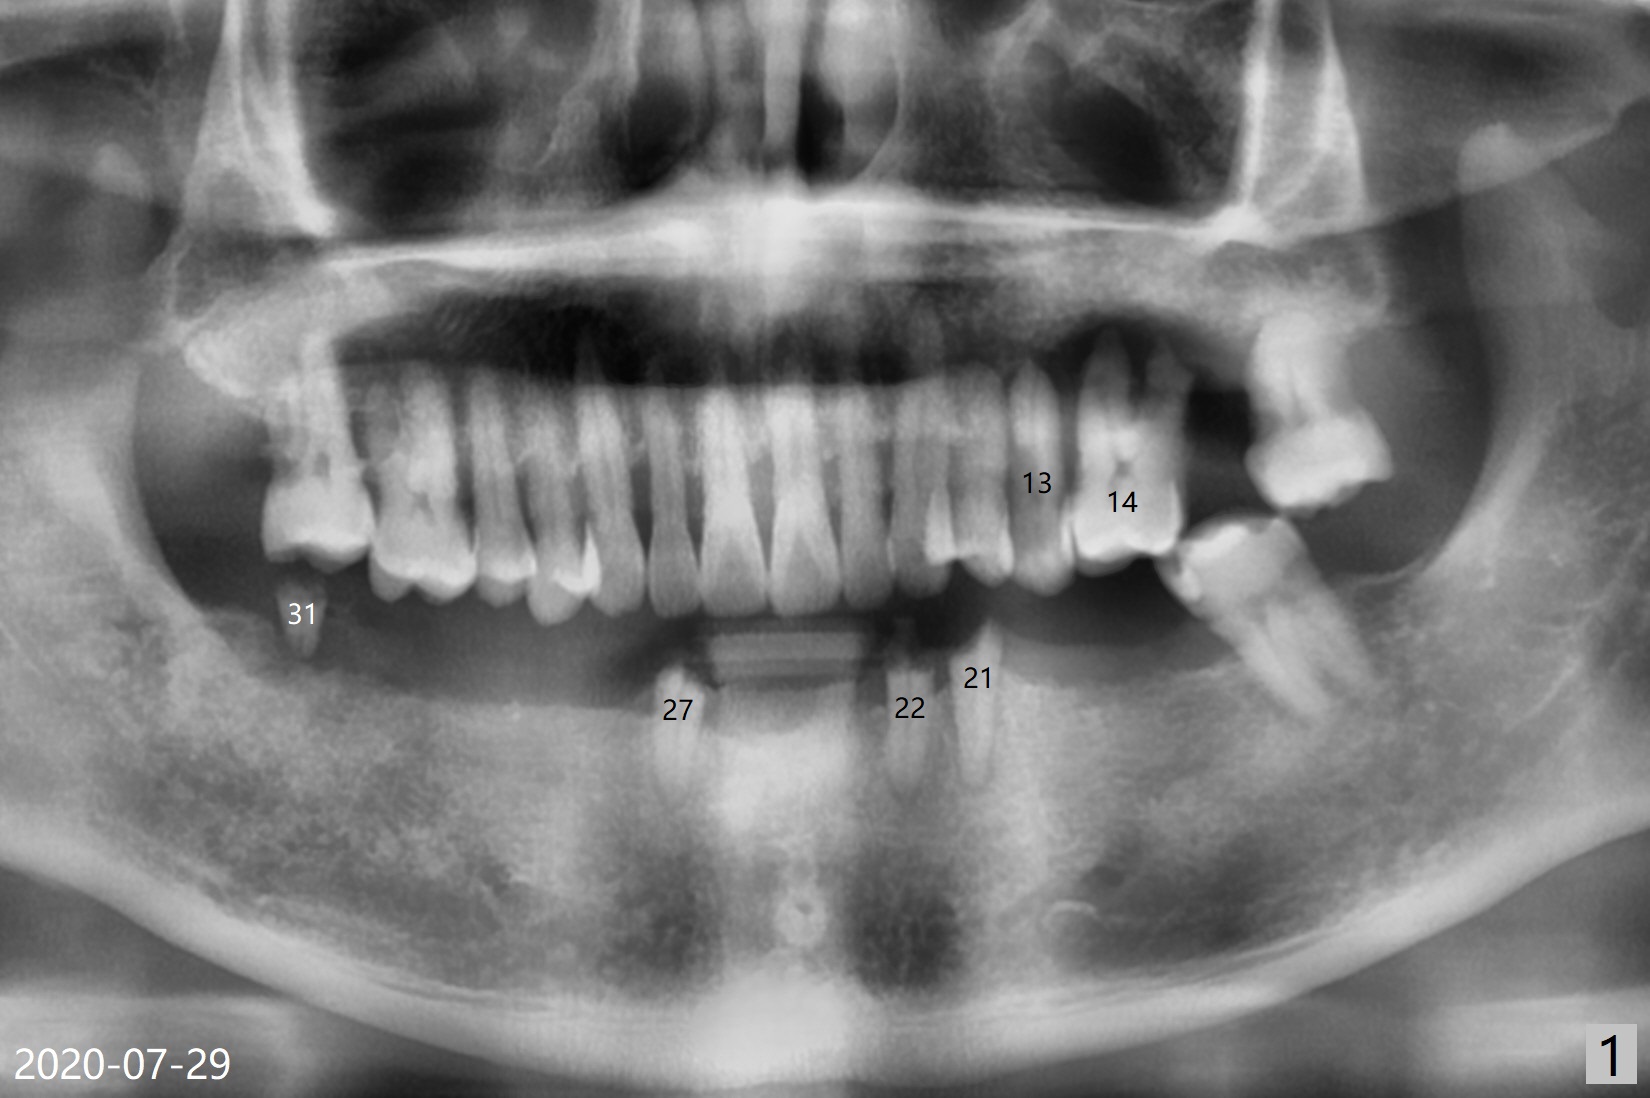

60岁男两年前回国制作下颌活动假牙,之后没有什么护理,五个基牙四个坏的厉害(图一(上面):21,22,27,31),初步计划:21,22,27号牙根管治疗(图二,三),31号牙拔除种植(申请保险,图四),都装上球状基台(ball abutment),增加托牙稳定性。当牙根基牙不行时,再逐步改做植牙。深洗和14号牙(图一)拔出后十四天病人回来进行27号牙(右下3)根管治疗(图五,六),工作长度13毫米,合适打桩做牙冠吗(原有局部托牙有卡环(Clasp and rest)?还是安置球冒更恰当?